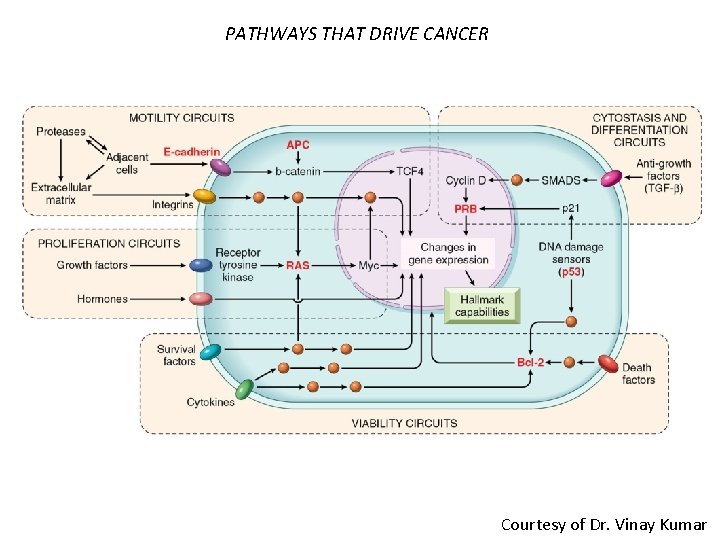

Targets of Genetic Damage • Proto-oncogenes: promote cell growth and are dominant in their action ( loss of one normal allele) • Tumor Suppressor genes: inhibit cell growth and are typically recessive ( loss of both alleles) but in some cases loss of one copy ( haploinsufficiency) is enough Courtesy of Dr. Vinay Kumar

Types of Mutations • Driver mutation: directly responsible for promotion of tumor growth (can be oncogene of tumor suppressor) and good target for drug development. Thought to be approximately 10 per tumor. Point mutations, amplifications and gene fusions. • Passenger mutation: occur randomly through genome due to DNA repair defects in tumor cells and do not contribute to cell growth. Thousands per lung cancer genome.

PATHWAYS THAT DRIVE CANCER Courtesy of Dr. Vinay Kumar